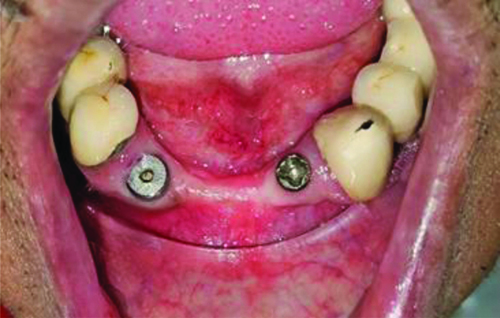

A 62-year-old male patient was referred to the Department of Prosthodontics at Bharati Vidyapeeth (Deemed to be University) Dental College and Hospital, Pune, Maharashtra, India, for the retrieval of a gingival former in the lower anterior region. An implant from COWELL® Implant Solution was placed in the regions of 33 and 43 at a private clinic approximately 11 months ago. The second stage surgery was performed seven months ago. Two gingival formers with a collar height of 2 mm were placed in the regions of 33 and 43. For the commencement of the prosthetic phase, the gingival formers needed to be removed.

Using a high-speed handpiece and a carbide bur, a plus-shaped groove approximately 2 mm in depth was created from the center by extending the access hole of the former under copious irrigation until the screwdriver fitted snugly [Table/Fig-1] [2]. A high vacuum suction was employed to prevent any particles of the former from being swallowed by the patient. The screwdriver from the Typodont jaw set was autoclaved before use in the patient’s mouth [Table/Fig-2].

Plus-shaped groove made on the gingival former using a carbide bur [2].